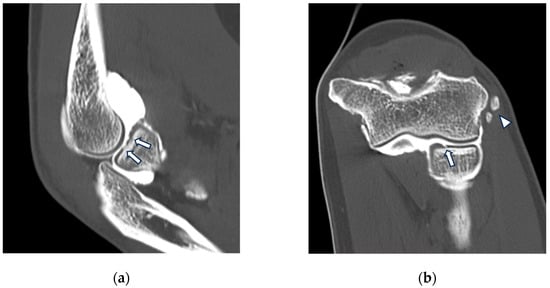

Acute trauma to the elbow most often leads to ligament tears, more commonly the LCL—in case of varus stress—and less commonly the MCL, in case of valgus stress [44]. This may be represented, for instance, by a fall on outstretched arm for the MCL. Full-thickness tears of the MCL or LCL can be identified on CT arthrography as discontinuity of the ligament with extravasation of intra-articular contrast medium into peri-articular soft tissues (Figure 5) [31]. While it is also important to detect partial ligament tears, as they may warrant surgical reconstruction in athletes, their diagnosis can be more difficult, especially on MR imaging [45]. Conversely, the higher spatial resolution of CT arthrography may yield a higher sensitivity, thus allowing the detection of focal ligament thinning and subtle permeation of the ligament by intra-articular contrast medium filling the tear and extending into the ligament due to fiber delamination [11]. The typical finding of a distal partial tear of the MCL is the so-called “T sign”, related to contrast permeation into the defect and extending distally between the MCL and the proximal aspect of the ulna [25]. Indeed, the anterior bundle of the MCL in normal conditions attaches about 3 mm distal to the proximal profile of the sublime tubercle; hence, a partial tear might be considered when contrast extends more than 3 mm distally [46]. In the setting of acute trauma, there are often concomitant injuries to adjacent structures, such as capsular disruption, fractures of the coronoid process, delamination of articular cartilage, and contusions [46]. The most reliable indication of traumatic disruption to the MCL is the finding of contrast extending medially beyond the joint line [46]. In the context of trauma, the tear’s specific location (proximal or distal) becomes less crucial, and such tears seldom need reconstruction.

Figure 5.

CT arthrography of a patient with sequelae of traumatic elbow dislocation. (a,b) Coronal and axial images showing LCL laxity with subtle foci of contrast medium permeation due to ligament delamination (white arrowheads) and a loose body within a pathologically distended lateral recess (white arrow), as well as cartilage thinning and fraying of the lateral aspect of the capitulum humeri (yellow arrowhead). Post-traumatic deformity of the radial head can also be seen; (c) sagittal reformat shows a loose bony fragment posterior to the capitulum humeri (asterisk) and posterior synovial thickening (yellow arrow).